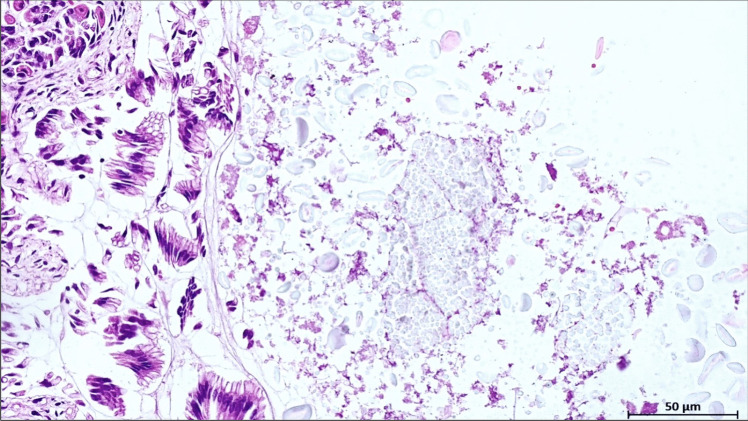

Sudden unexpected infant death (SUID) encompasses both explained and unexplained infant fatalities. When a comprehensive investigation yields inconclusive results, the case is classified as sudden infant death syndrome (SIDS). On the other hand, the most frequent non-SIDS diagnoses may be attributed to specific causes of death including a heterogeneous spectrum of conditions and disorders (e.g., trauma, asphyxia, suffocation, infection and metabolic diseases). Although rare, milk aspiration is a recognized cause of SUID that can lead to acute respiratory failure. This case report describes the death of a three-month-old infant found unresponsive in a traditional African baby carrier. Gross examination revealed no significant anomalies other than increased lung weight and the presence of milk-like material in the airways, alveoli, and stomach. Histological and ultrastructural analyses identified granular brownish material with birefringent globules in the lungs, consistent with aspirated milk. Immunohistochemical staining was positive for beta-lactoglobulin, confirming formula milk aspiration. This evidence was crucial in excluding maternal negligence as a cause of death, instead supporting an ante-mortem aspiration event resulting from regurgitation. This case highlights the diagnostic challenges associated with fatal milk aspiration and emphasizes the critical importance of a multidisciplinary approach. The integration of clinical history, autopsy findings, and advanced histopathological techniques is essential for accurately determining the cause of death and ensuring a sound legal assessment within the Courtroom setting.

婴儿意外猝死(SUID)包括可解释的和无法解释的婴儿死亡。当全面调查没有得出确定的结果时,该病例被归类为婴儿猝死综合征(SIDS)。另一方面,最常见的非小岛屿发展中国家诊断可归因于具体的死亡原因,包括各种各样的病症和失调(例如,创伤、窒息、窒息、感染和代谢疾病)。虽然罕见,吸乳是SUID的公认原因,可导致急性呼吸衰竭。本病例报告描述了一名三个月大的婴儿在传统的非洲婴儿背带中发现无反应死亡。大体检查除肺重量增加及气道、肺泡和胃内有乳样物质外,未见明显异常。组织学和超微结构分析发现肺部有褐色颗粒状物质,有双折射球,与吸乳一致。免疫组化染色-乳球蛋白阳性,证实误吸配方奶。这一证据对于排除产妇疏忽作为死亡原因,而不是支持由反流引起的死前误吸事件至关重要。本病例强调了与致命吸乳相关的诊断挑战,并强调了多学科方法的关键重要性。综合临床病史、尸检结果和先进的组织病理学技术对于准确确定死亡原因和确保在法庭环境下进行合理的法律评估至关重要。